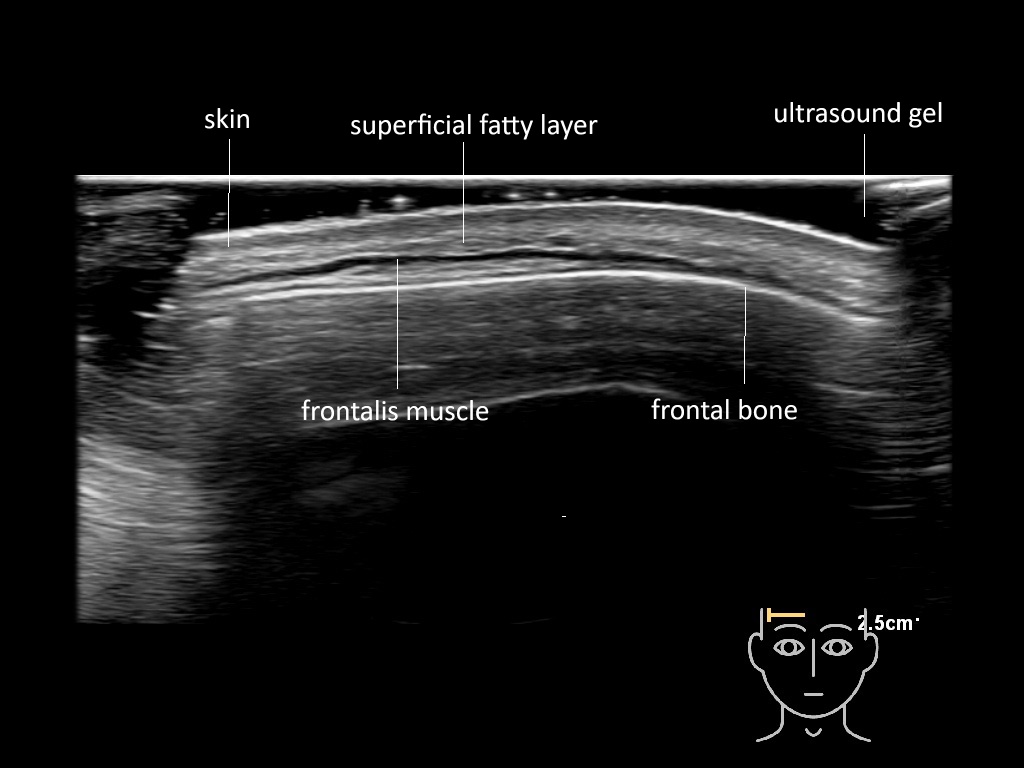

In this section you will learn more about the different layers of the face with the use of ultrasound. When you click on the secondary ultrasound image, you will see the different structures as an overlay. This will help to train yourself to recognize the different layers of the face.

Study the first image to recognize the different layers. If you are sure about the layers, swipe to the second image to view the answer (if applicable).